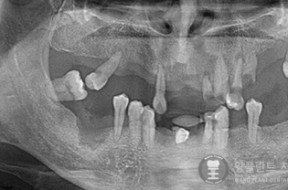

전후사례